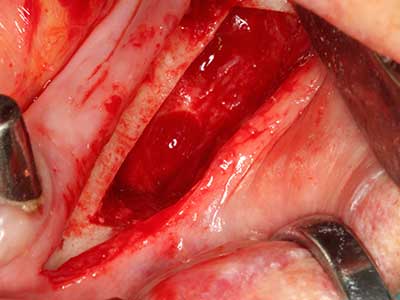

Когато се извършват хирургични процедури върху кост в непосредствена близост до чувствителни структури като кръвоносни съдове или нерви, ротиращите инструменти създават значителен риск за ятрогенно нараняване. Пиезоелектрическите апарати могат да бъдат от помощ при препарация на костно покритие и отстраняване на твърда кост близо до нерви, особено за оголване на нервите след ятрогенно нараняване, както и по време на латерализация на нервите за резекционни и реконструктивни процедури или поставяне на имплант (Фиг. 17-20). Лекият контакт между пиезонакрайника и нерва по принцип не води до нараняване, но ако действате непредпазливо с трионообразни движения или приставки за остатъчен костен субстрат, може да причините временно или перманентно увреждане на нерва. Въпреки това, рискът от увреждане се счита за много по-малък, отколкото при употреба на триони или ротиращи инструменти (Pereira, Gealh et al. 2014).